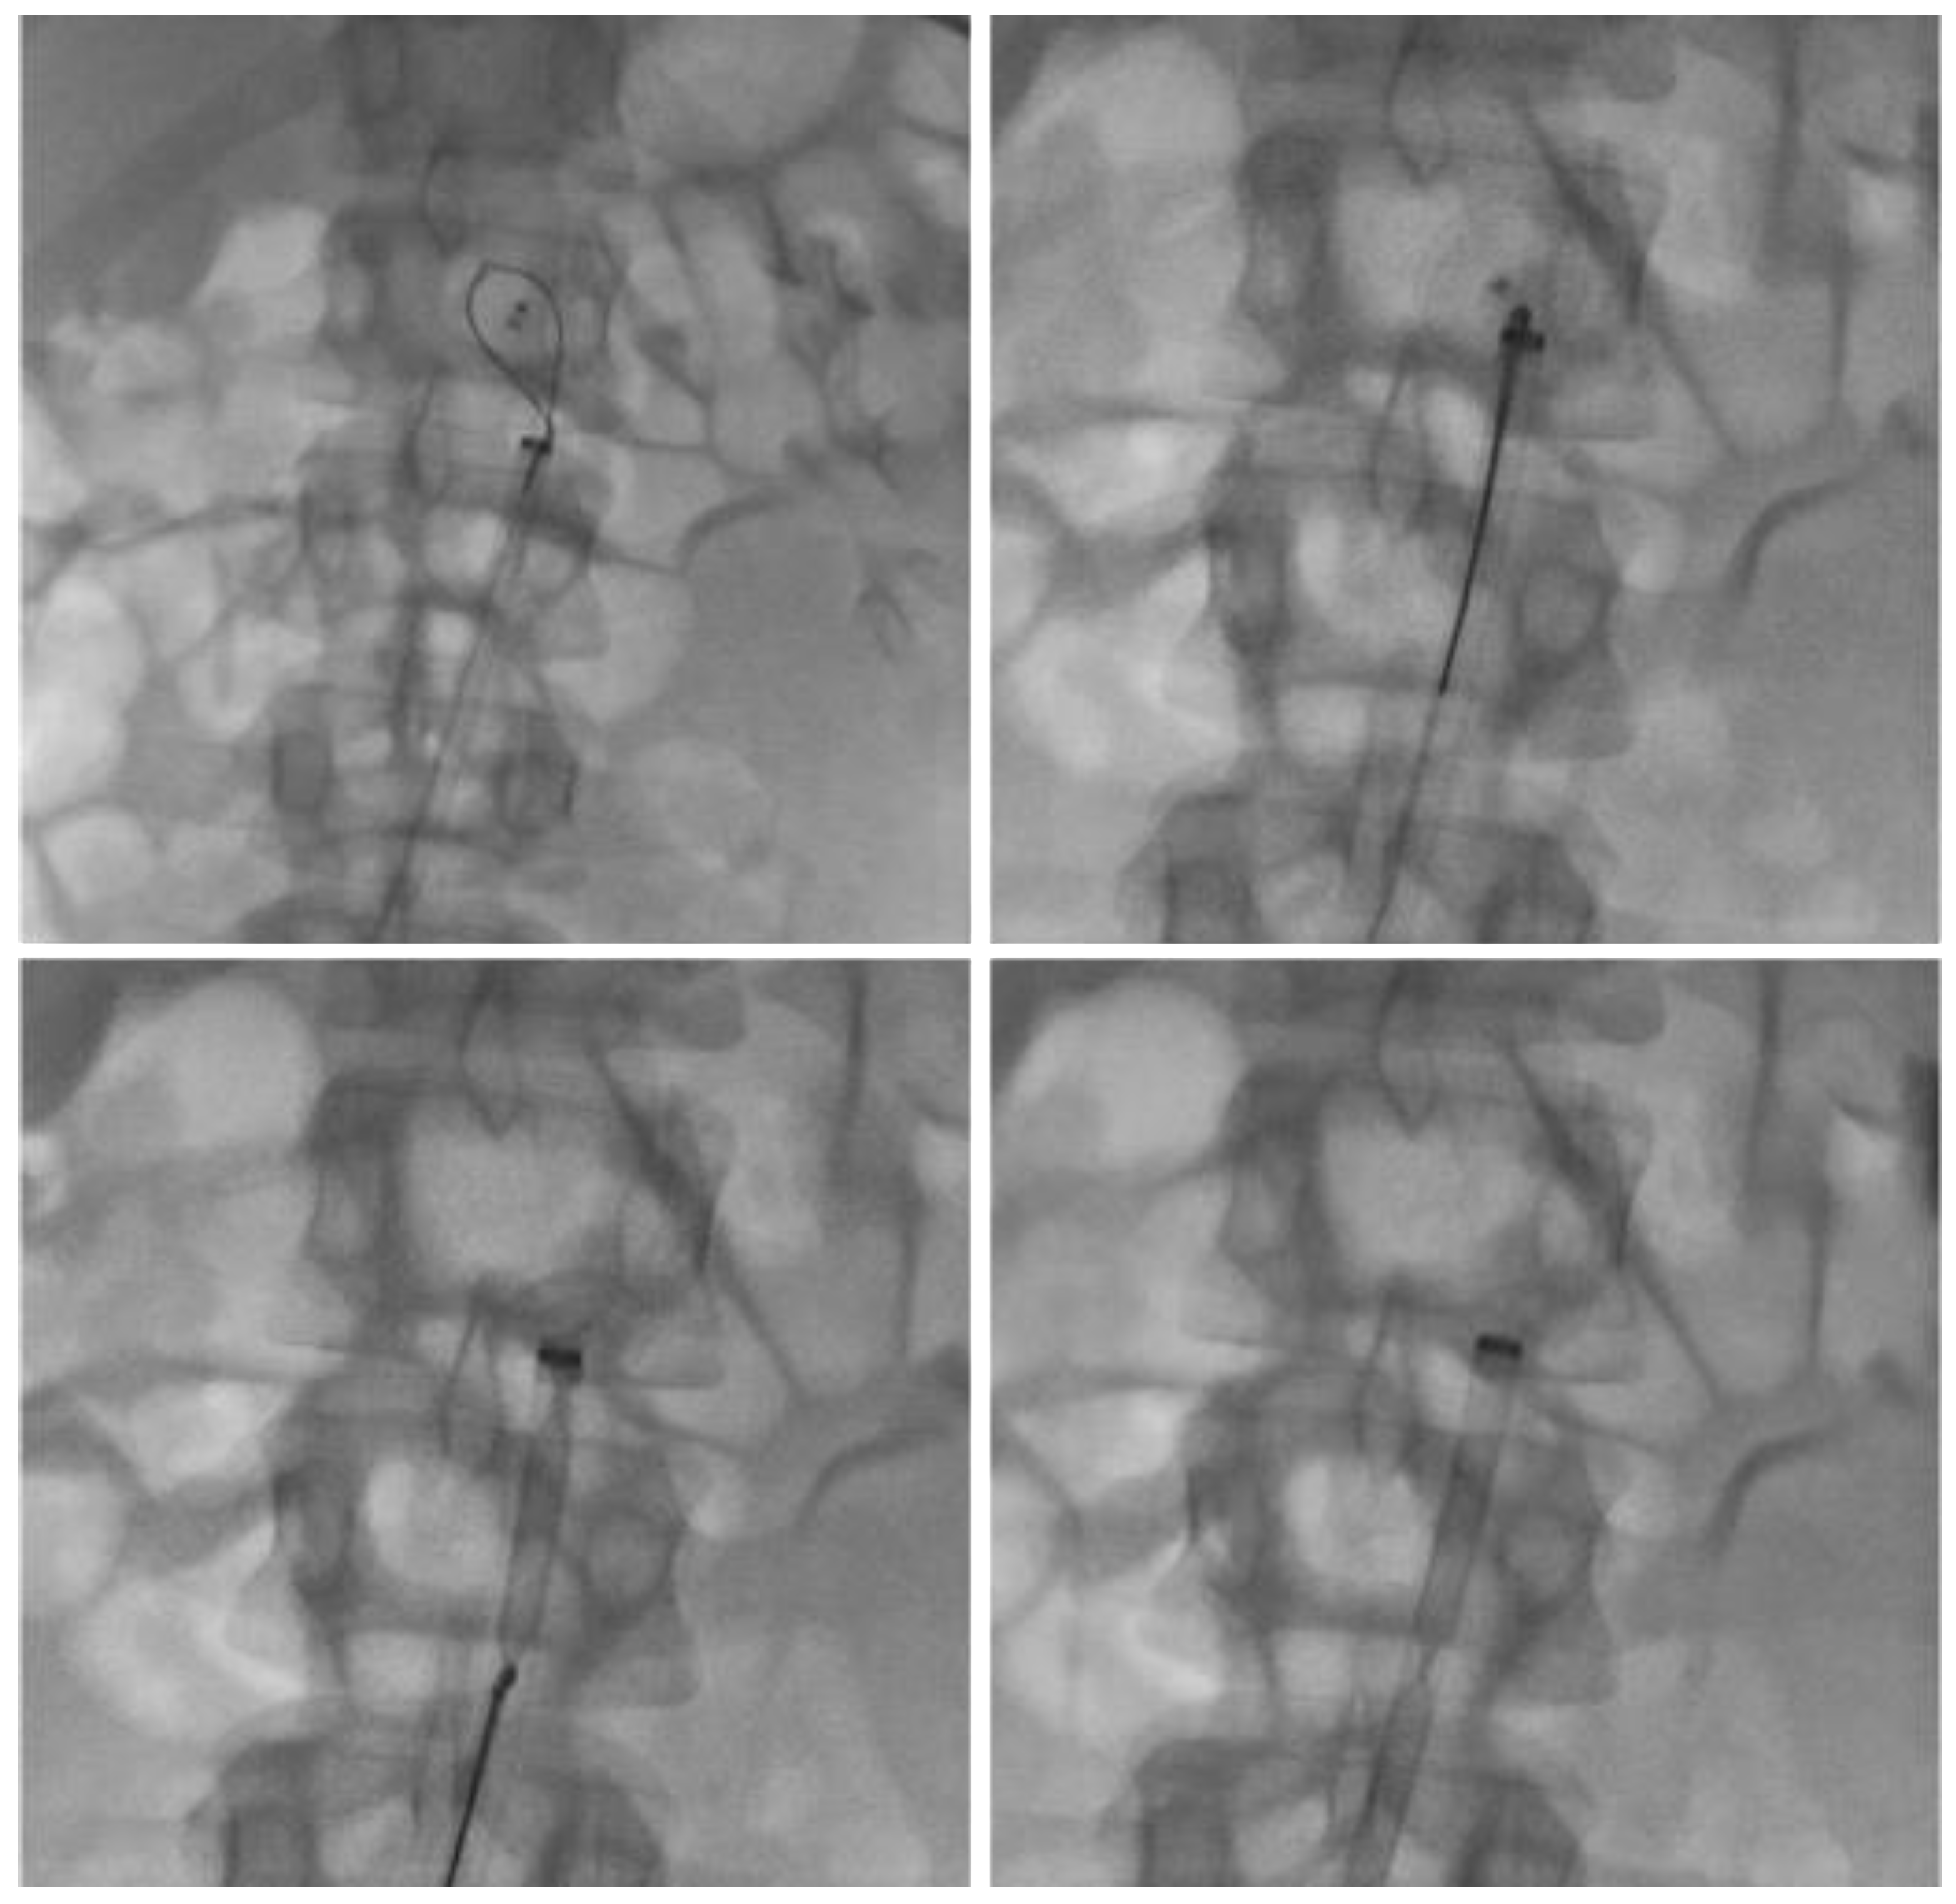

The procedure was performed under local anesthesia via right common femoral artery access. Diagnostic aortography confirmed the presence of the device lodged within the infra-renal abdominal aorta, without impairment of aorto-iliac flow. Using a snare retrieval system, the device was successfully captured and removed through a large-bore introducer sheath. Final angiographic control demonstrated normal patency of the abdominal aorta, renal arteries, and iliac vessels, with no procedural complications (Figure 3).

Figure 3. Endovascular retrieval of the migrated Amplatzer device using a snare system via right common femoral artery access. Final angiographic control shows complete removal of the device and preserved patency of the abdominal aorta and iliac vessels.